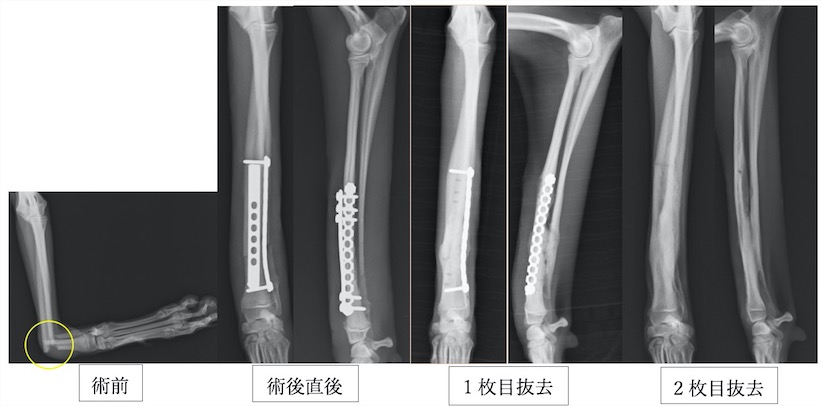

近年、小型犬が増加しているのに比例して橈尺骨骨折が増加しています。橈尺骨骨折にはプレートを2枚入れる方法を用います。2枚入れることで強度を増すことができプレートの破綻を防止できます。また、1枚ずつプレート抜去が可能であるため、ある程度骨が固まってきたら1枚抜去し、さらに骨化を促進し、もう一枚抜去するという方法が可能です。そうすることで癒合不全(骨化が遅れること)を防止し、プレート抜去後の再骨折のリスクを減らすことができます。

イタリアングレーハウンドの橈尺骨骨折です。2.0mmスクリューを使用しています。

トイプードル9歳の橈尺骨骨折です。1.5mmスクリューを使用しています。

トイプードル2歳の橈尺骨骨折です。1.5mmスクリューを使用しています。

上の3症例ともにやや中央寄りの先端部の橈尺骨の横骨折(遠位骨幹部橈尺骨横骨折)です。直線のプレートを使用しています。

ポメラニアン半年齢の橈骨尺骨骨折です。1.3mmの超小型スクリューを使用しました。

上の4症例はやや中央寄りの先端部の橈尺骨の横骨折(遠位骨幹部橈尺骨横骨折)です。直線のプレートを使用しています。